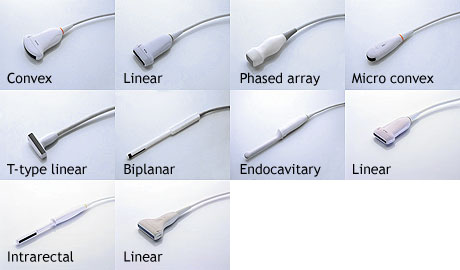

The patient should be supine, with a low frequency probe, Curvilinear

The 'ECHO" Phased array probe can provide the additional benefit of visualizing between the ribs & getting into the sub xiphoid region more easily for the cardiac view and the Linear probe can make the lung/PTX views easier.

A high frequency linear probe is ideal for this exam.